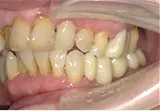

| 年齢/性別 | 50代女性 |

| 主訴 | 左下奥歯に痛みがある、全体的に治したい |

| 治療内容 | 全体的に歯周病やむし歯、根の治療を行い、仮歯を使用して咬合治療を実施。右下2本、左下1本の計3本を抜歯し、その後、右下に2本、左下に2本の計4本のインプラントを埋入しました。 |

| 治療期間 | 8か月 |

| 費用 | 2,106,500円税込 |

| リスク・副作用 | 炎症反応によって術後に腫れが生じることがあります。その程度は、手術の範囲や方法によって異なりますが、多くの場合、時間の経過とともに徐々に治まります。 ごく稀に、下顎奥歯の外科手術後に、唇や顎に痺れを感じることがあります。 |